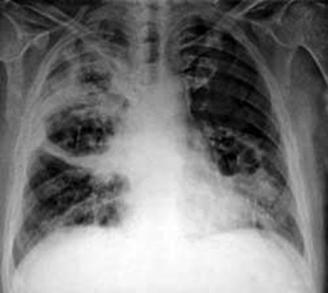

Derrame pericárdico severo da imagen en botellón en la radiografía de tórax. (ENAM EXTRA 2021)

Radiología:

Cardiomegalia

Radiografía: cardiomegalia con hipertensión venosa pulmonar